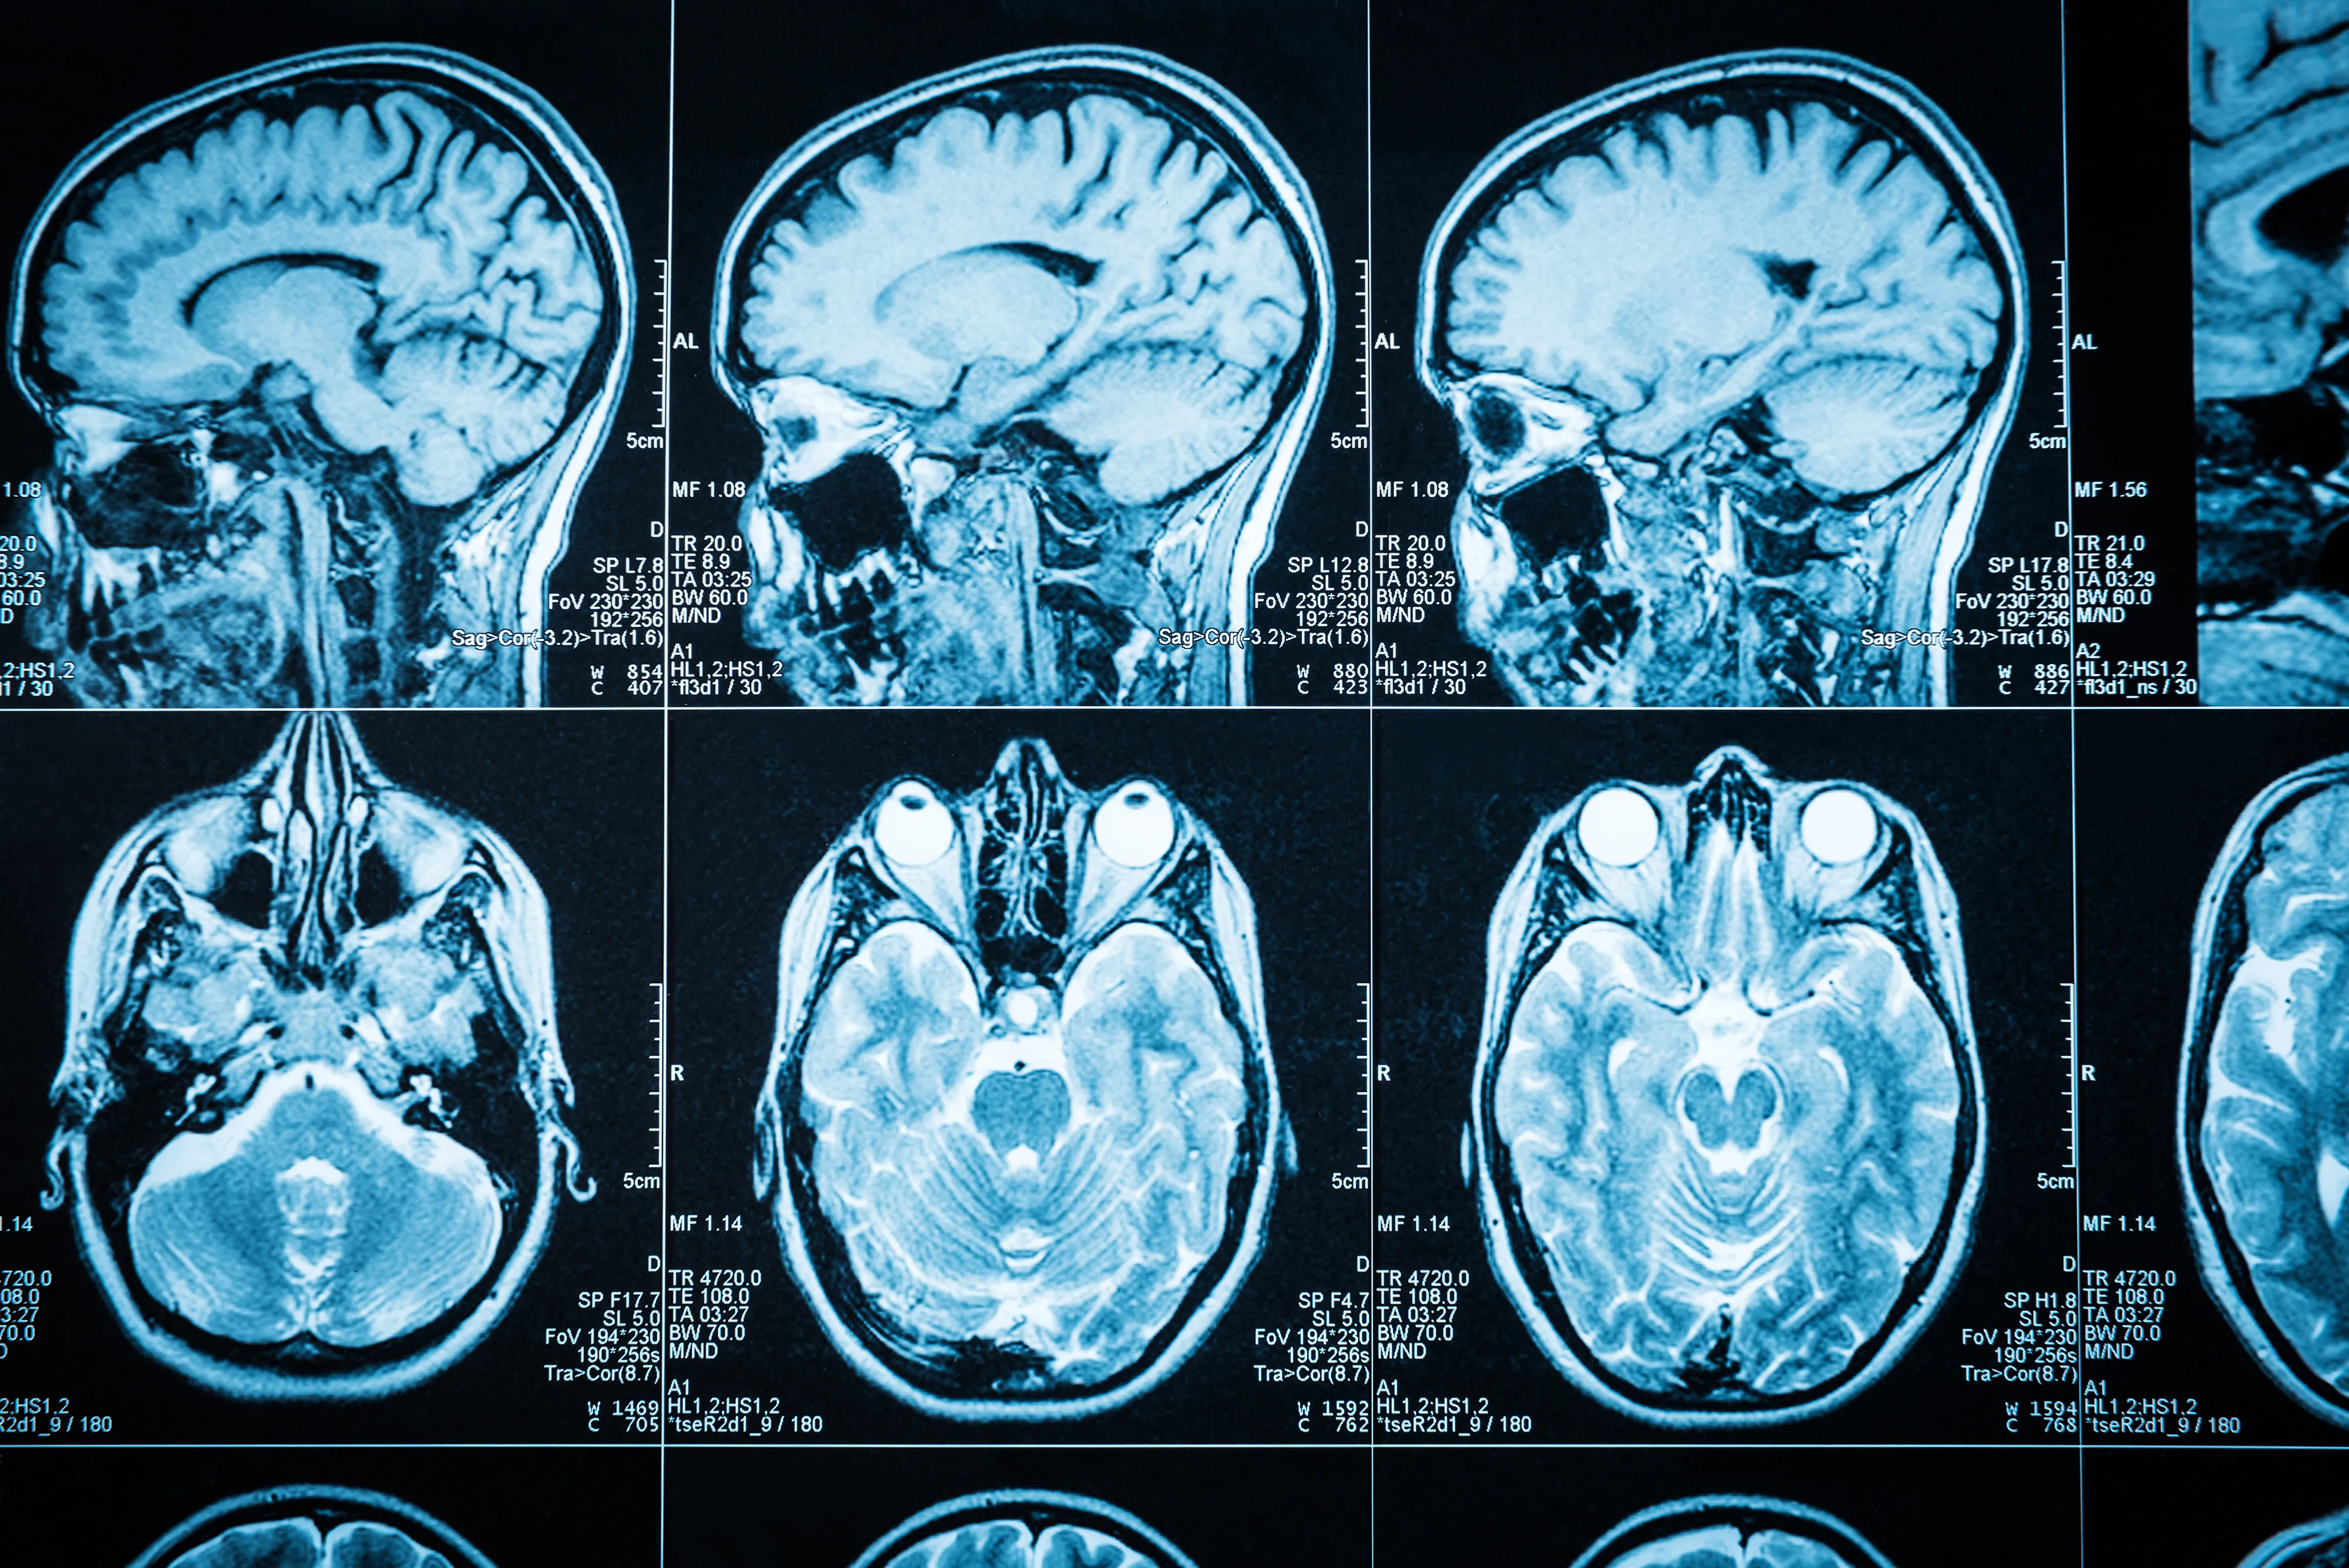

Image credit: Trifonov_Evgeniy/Getty Images